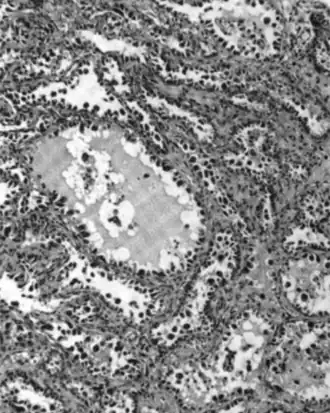

Micrograph of a mucinous ovarian carcinoma stained by H&E | |

Mucinous adenocarcinoma

Mucinous adenocarcinomas make up 5–10% of epithelial ovarian cancers. Histologically, they are similar to intestinal or cervical adenocarcinomas and are often actually metastases of appendiceal or colon cancers. Advanced mucinous adenocarcinomas have a poor prognosis, generally worse than serous tumors, and are often resistant to platinum chemotherapy, though they are rare.[29]